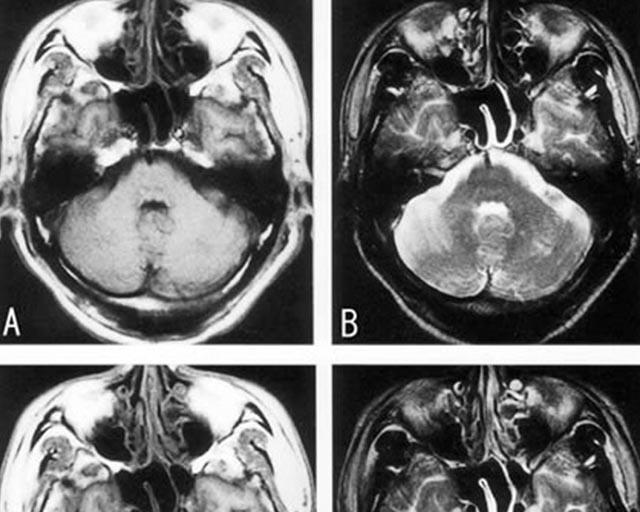

画像所見はMRIでT1画像で動脈壁の三日月状高信号(壁在血栓)やMRAで

pearl and strings signやflap形成が見られる。